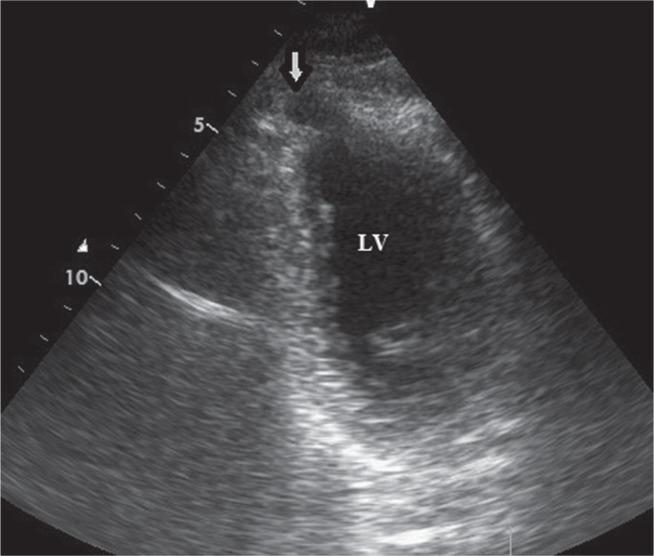

Isolated congenital left ventricular diverticulum presenting as stable angina pectoris and surgical treatment.

Kardiochir Torakochirurgia Pol. 2019 Mar;16(1):44-46. doi: 10.5114/kitp.2019.83946. Epub 2019 Apr 4.